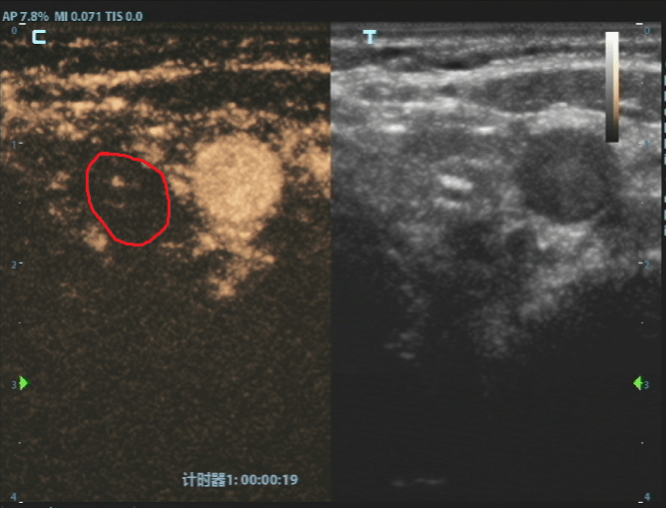

消融前病灶

经过严谨评估,刘女士首先接受了甲状腺穿刺活检。病理结果证实了最坏的猜想——甲状腺乳头状癌。但紧随其后的详细评估,却带来了好消息,结节微小、单发、未转移、未侵犯包膜,完全符合射频消融治疗的黄金指征。

这个方案瞬间让刘女士放下了所有的担忧。随后,白国栋主任团队便为她实施了超声引导下甲状腺结节射频消融术,整个过程仅十几分钟。治疗结束时,刘女士几乎不敢相信地说,“就这么好了?我根本没有任何不舒服的感觉。”

消融后病灶